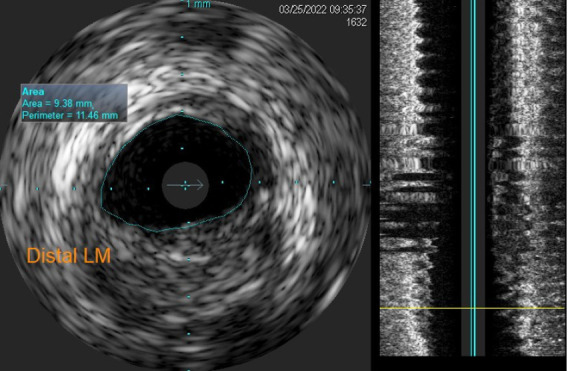

Planning and guiding PCI in a complex intervention is very important and one of the most important decisions is the one on whether to use one or two stent bifurcation techniques. Unfortunately, this can easily turn into complication and the need to alter the procedural strategy. The main points to be considered when deciding on the PCI strategy are related to both procedural safety and long-term outcomes. Provisional stenting has been recommended as the default technique for most coronary bifurcation lesions. In this paper, we describe the case of a patient scheduled for elective procedure of bifurcation lesion of LAD/D1. Our planned strategy was provisional stenting of LAD, using one stent for LAD, DCB for D1. Due to the complication that occurred, i.e., dissection of LAD after LAD stenting, we changed the strategy to two-stents technique strategy, using Culotte technique.

在复杂的介入治疗中规划和指导PCI是非常重要的,其中最重要的决定之一是是否使用一种或两种支架分叉技术。不幸的是,这很容易变得复杂,需要改变程序策略。在决定PCI策略时要考虑的要点与手术安全性和长期结果有关。临时支架置入术被推荐为大多数冠状动脉分叉病变的默认技术。在本文中,我们描述的情况下,病人计划择期手术的分叉病变的LAD/D1。我们计划的策略是LAD临时支架置入,LAD使用一个支架,D1使用DCB。由于LAD支架置入术后LAD发生夹层等并发症,我们将策略改为双支架技术策略,采用Culotte技术。